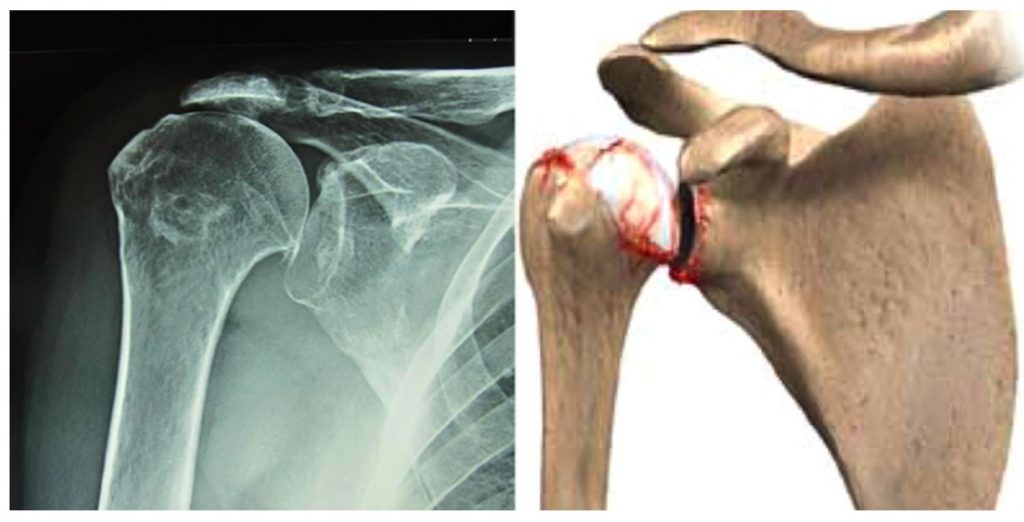

Shoulder Osteoarthritis Orthopaedic Center Of Southern Illinois

Mr Paul Jarrett Acromioclavicular Joint Arthritis or Arthropathy Shoulder Surgery Osteoarthritis Shoulder arthroscopy is a minimally invasive surgery to treat shoulder problems, including shoulder impingement and rotator cuff. Shoulder replacement surgery is typically reserved for advanced arthritis of the shoulder joint, but can also be used for complex fractures and other problems that cannot be. Surgery is an invasive treatment option for people with osteoarthritis (oa) where a joint (usually the. Shoulder Surgery Osteoarthritis.

Left shoulder with advanced glenohumeral osteoarthritis before and Shoulder Surgery Osteoarthritis Shoulder arthroscopy is a minimally invasive surgery to treat shoulder problems, including shoulder impingement and rotator cuff. Physical therapy is necessary to. The most common reasons for a shoulder replacement surgery are osteoarthritis, rotator cuff tear arthropathy, avascular necrosis or rheumatoid arthritis. If your shoulder osteoarthritis pain becomes severe and you lose significant use of your shoulder, a doctor may. Shoulder Surgery Osteoarthritis.